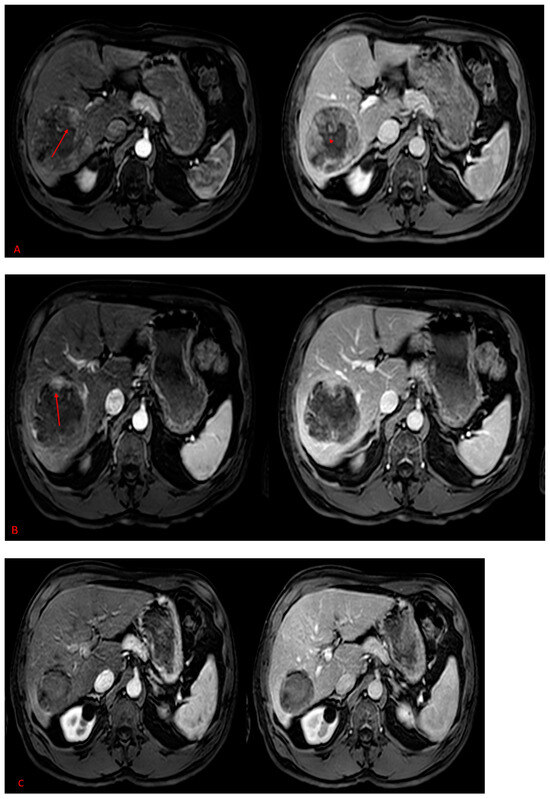

2. Results

3. Discussion

4. Methods and Materials